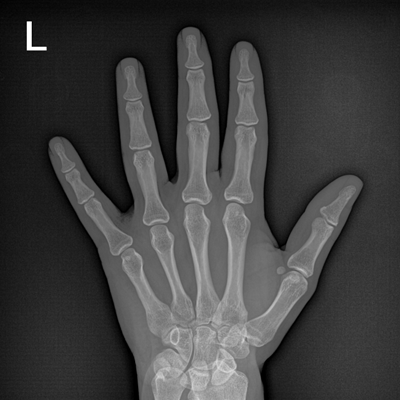

輕量化設(shè)計(jì) 小巧靈活 PLX5100

用于影像科、急診室、病房、ICU、手術(shù)室等多場(chǎng)景應(yīng)用。

● 數(shù)字化無(wú)線平板成像,操作簡(jiǎn)便,成像質(zhì)量高